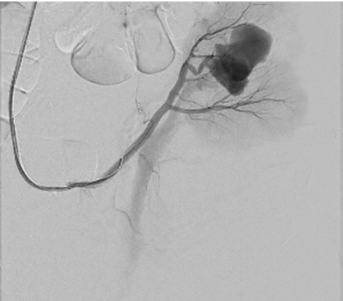

Right femoral artery was punctuated under local anesthetic. Inferior segmental artery was selectively catheterized and pseudoaneurysm was visualized. A microcatheter was inserted into segmental branch (Figure 4).

Pseudoaneurysm was embolized with two 8 mm x 20 cm coils, an additional coil of 12 mm x 30 cm (Figure 5).

Control angiography with contrast was performed. Pseudoaneurysm was completely occluded and no longer visible (Figure 6). No extravasation was found.

After embolization, creatinine decreased till 83 µmoL/L and eGFR was 73 mL/min/1.73 m2. Pseudoaneurysm was no longer visible, as well as small segmental branches. Vascularization of renal parenchyma is reduced.